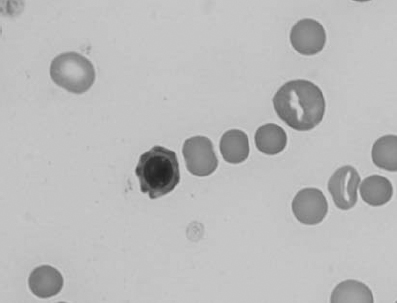

Figure 1.3 Canine blood film showing acanthocytes (also see color section).

Figure 1.4 Canine blood film showing anisocytosis (also see color section).

Figure 1.5 Bovine blood film showing basophilic stippling within a macrocyte as part of the regenerative response (also see color section).

Figure 1.6 Canine blood film showing basophilic stippling due to lead toxicosis (also see color section).

Figure 1.7 Canine blood film showing blister cells due to oxidative damage (also see color section).

Figure 1.8 Canine blood film showing codocytes. Up to 50% codocytes may be normal in a dog (also see color section).

Figure 1.9 Canine blood film showing eccentrocytes due to oxidative damage (also see color section).

Figure 1.10 Canine blood film showing echinocytes I (also see color section).

Figure 1.11 Canine blood film showing echinocytes III (also see color section).

Figure 1.12 Feline blood film showing echinoelliptocytes (also see color section).

Figure 1.13 Canine blood film showing Heinz bodies and ghost cells due to oxidative damage. There are also several polychromatophils (also see color section).

Figure 1.14 Canine blood film stained with new methylene blue, to demonstrate Heinz bodies (also see color section).

Figure 1.15 Canine blood film showing keratocytes and schizocytes (erythrocyte fragments) due to fibrin strand injury. A codocyte and a polychromatophil also appear in the field (also see color section).

Figure 1.16 Feline blood film showing Mycoplasma hemofelis organisms (hemobartonellosis). Organisms are not always visible in blood smears from infected cats (also see color section).

Figure 1.17 Canine blood film showing several macrocytes (also see color section).

Figure 1.18 Canine blood film showing a metarubricyte There is also a polychromatophilic macrocyte in the field (also see color section).

Figure 1.19 Canine blood film showing microcytic, hypochromic erythrocytes consistent with iron deficiency anemia. There are two polychromatophils in the field, indicating that the anemia is regenerative (also see color section).

Figure 1.20 Canine blood film showing two macrocytes with nuclear remnants (also see color section).

Figure 1.21 Bovine (calf) blood film showing marked poikilocytosis (normal?) (also see color section).

Figure 1.22 New methylene-blue-stained Canine blood film showing reticulocytes (also see color section).

Figure 1.23 Canine blood film showing rouleaux formation (also see color section).

Figure 1.24 Canine blood film showing spherocytosis and polychromasia due to immune-mediated hemolytic anemia (also see color section).

Figure 1.25 The red blood cell cytoskeleton.